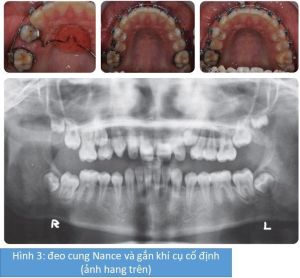

Khí cụ Twin Block đảo ngược được sử dụng để giải quyết tương quan răng cửa trong vòng 7 tháng. Sau đó, cung khẩu cái Nance tùy chỉnh được lắp cùng với khí cục cố định hàm trên phân đoạn để bắt đầu di xa R16. Sau đó, gắn toàn bộ các khí cụ cố định hàm trên và hàm dưới đẻ hoàn thành việc tái tạo khoảng cho các răng ngầm và hoàn thiện quá trình làm đều cung răng.

Quá trình điều trị được thể hiện qua hình 2, hình 3